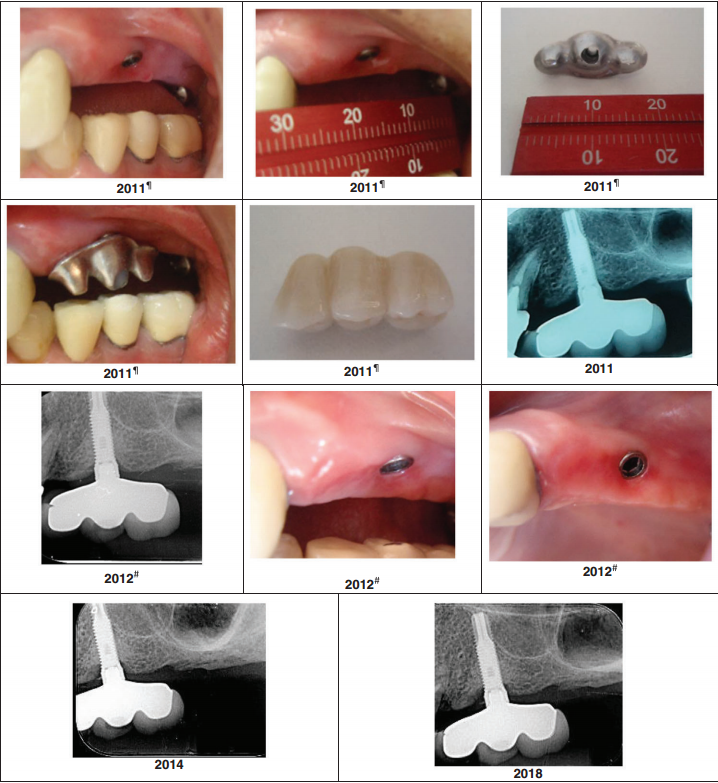

The case study published in Clinical Advances in Periodontics (2024) represents one of the most carefully documented consecutive case series in modern implant dentistry. Forty-three implants in 37 patients — non-diabetic, non-smokers, spanning both maxilla and mandible, predominantly in the posterior region — were followed for an average of 7.2 years, with the longest cases exceeding a decade.

These were not ideal cases selected to flatter the results. Many involved implants placed in the absence of perfect parallelism conditions that would typically necessitate complex surgical or prosthetic workarounds. The TA abutment was chosen precisely because it functions where traditional systems require compromises.

To put the marginal bone loss figure in context: the threshold conventionally cited as compatible with peri-implant health in prospective studies is approximately 0.1–0.2 mm annually. The TA cases averaged 0.022 mm per year — a figure that not only clears the threshold but suggests the hyperbolic paraboloid geometry may actively promote bone homeostasis rather than merely tolerating it.

The radiographic panels in the published paper are equally compelling. At final examination, images show no angular bone defects, no craters, and favorable cortical thickness and trabecular mineralization — characteristics more commonly associated with pristine natural teeth than with prosthetic implant sites approaching a decade of function.

Triple Abutment 7 year follow up by Dr. Luciana and her team